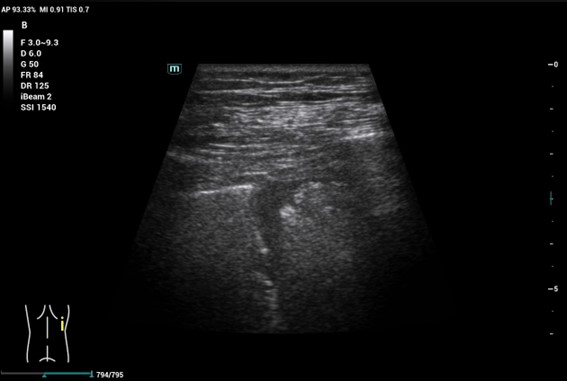

Durante su estancia en el centro de salud, realizamos una ecografía POCUS. Comenzamos explorando ambos miembros inferiores con adecuada compresibilidad del cayado, vena femoral y poplíteas y Doppler en su interior. Posteriormente continuamos con una ecocardioscopia donde no vimos dilatación de cavidades derechas. Finalmente llevamos a cabo un barrido en todos los campos pulmonares posteriores, objetivando en la base derecha, derrame pleural de pequeña cuantía y una imagen hipoecoica de morfología triangular con base hacia la pleura, sugerente de infarto pulmonar (Imagen 1).